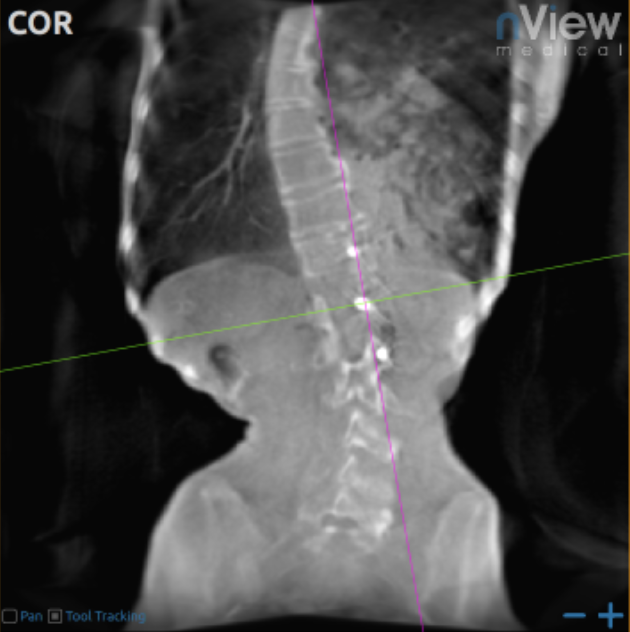

nView IMAGING OF THE LUNG - X-RAY SCATTER AND TOMOSYNTHESIS ARTIFACTS LIMIT CONTRAST IN THE LUNG